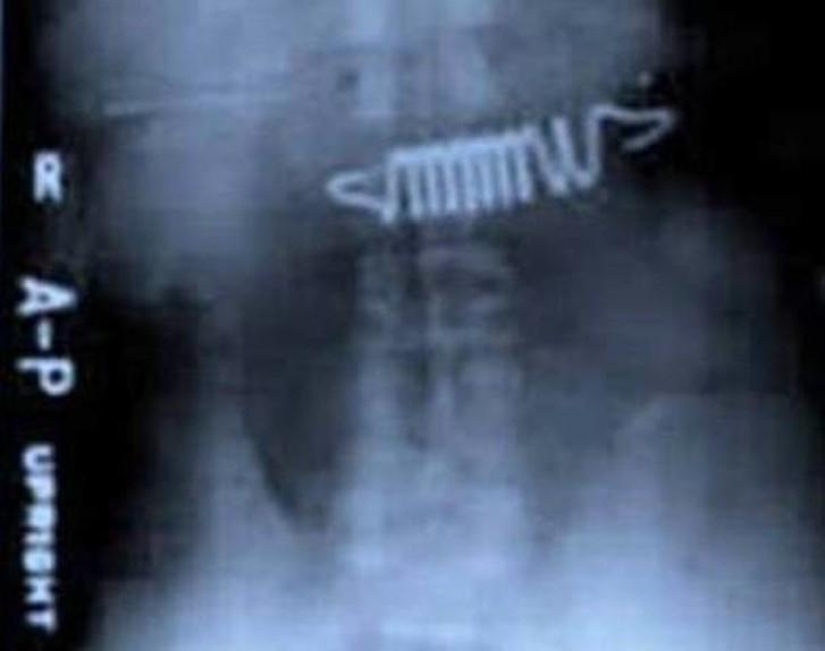

19. Resortes de la cama.